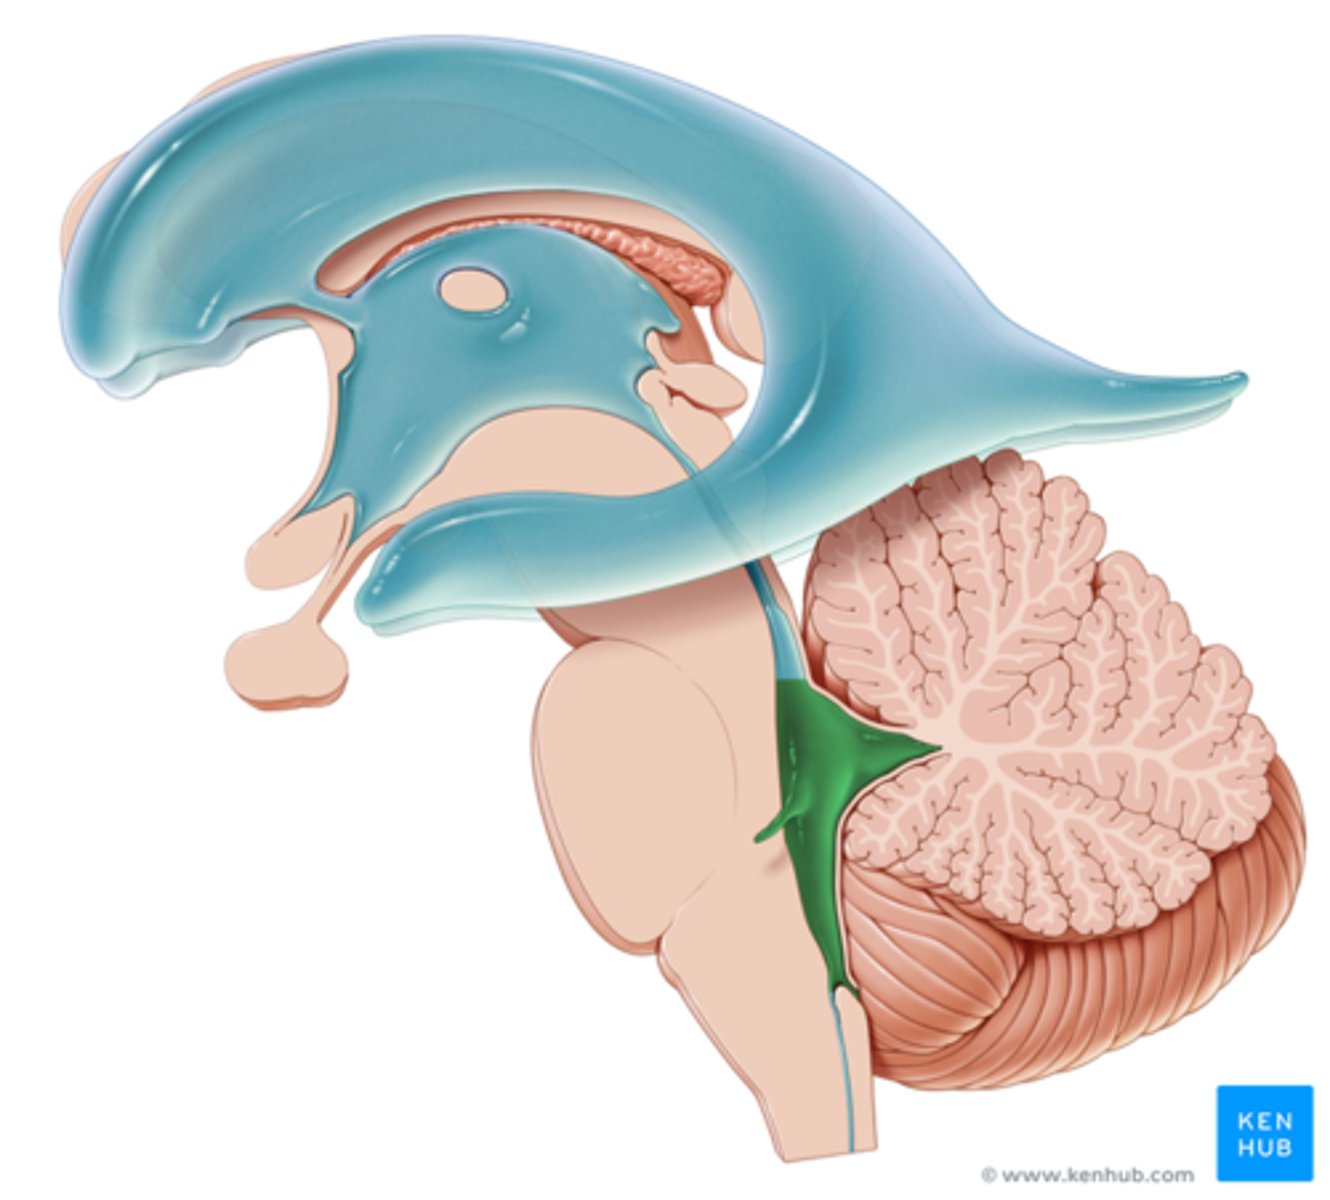

right and left lateral ventricles

third ventricle

fourth ventricle

cerebral aqueduct (mesencephalic aqueduct)

interventricular foramen

cerebellum

cerebellar cortex

arbor vitae

white matter